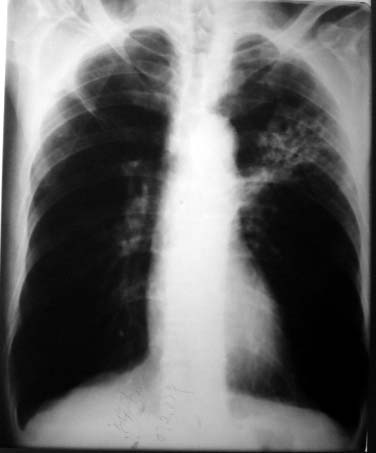

以下是引用liuzheng_9326在2007-9-4 16:23:00的发言:[br]痰检未见结核菌, 治疗后症状好转。图像符合陈旧性结核伴感染。

以下是引用拾荒者在2007-9-4 22:41:00的发言:[br][quote]以下是引用liuzheng_9326在2007-9-4 16:23:00的发言:[br]痰检未见结核菌, 治疗后症状好转。图像符合陈旧性结核伴感染。